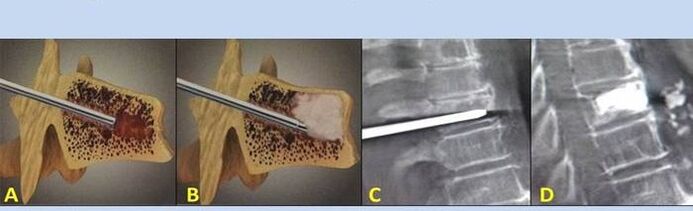

- Πυρηνοπλαστική – αφαίρεση του πυρήνα του μεσοσπονδύλιου δίσκου. Η επέμβαση ανακουφίζει από την πίεση στις νευρικές απολήξεις.

- Παρακέντηση σπονδυλοπλαστικής – μέθοδος σταθεροποίησης των σπονδύλων. Κατά τη διάρκεια της διαδικασίας, ο γιατρός γεμίζει τις κοιλότητες της σπονδυλικής στήλης με οστικό τσιμέντο.